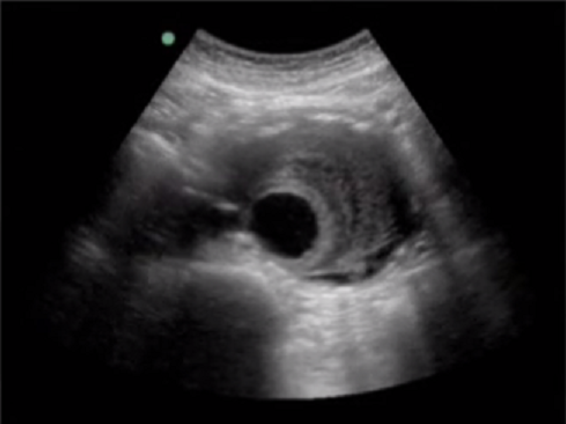

RUSH 腹部主动脉 2 图像